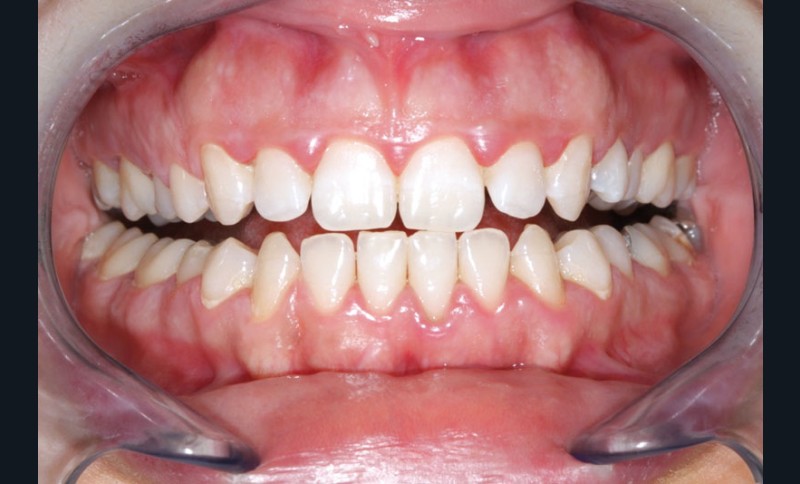

Ainsi, lors des périodes de désordres hormonaux, comme la puberté, la grossesse et la ménopause, on observe fréquemment des inflammations exacerbées qui peuvent révéler une susceptibilité de l’hôte aux maladies parodontales. (fig. 2 et 3).

Souvent, les signes cliniques régressent spontanément lorsque…